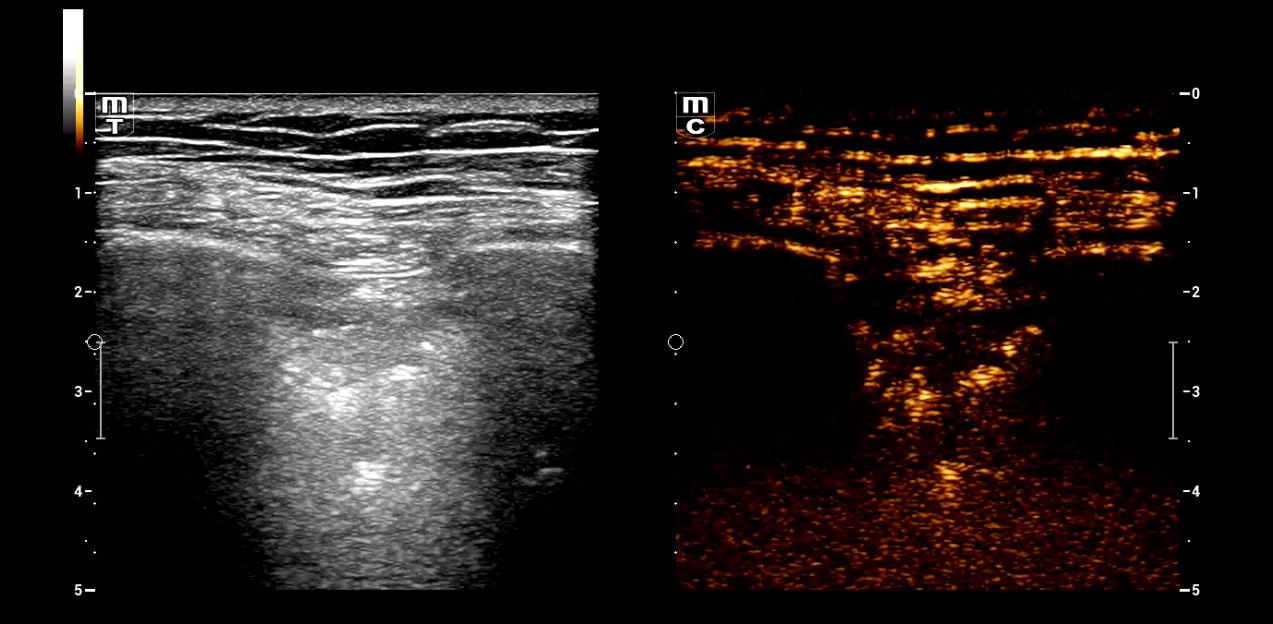

5. Residual thrombosis in the right popliteal vein. The compression test is positive in the dynamic examination.